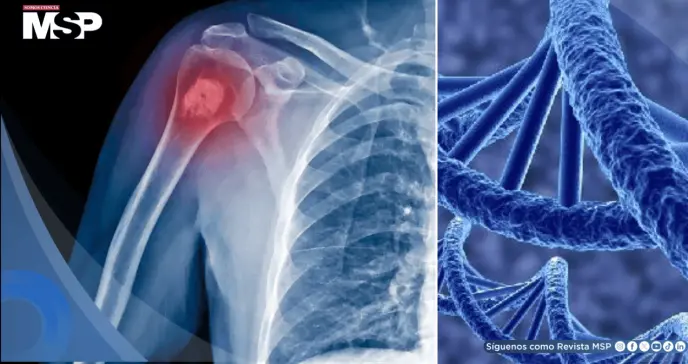

Entre ellos, el gen SMARCAL1 destacó como un nuevo factor de riesgo para el osteosarcoma, una enfermedad que afecta principalmente los huesos largos de brazos y piernas durante la adolescencia.

El osteosarcoma suele originarse en los huesos largos de brazos y piernas, y sus síntomas incluyen dolor persistente, inflamación o bultos, e incluso fracturas espontáneas.